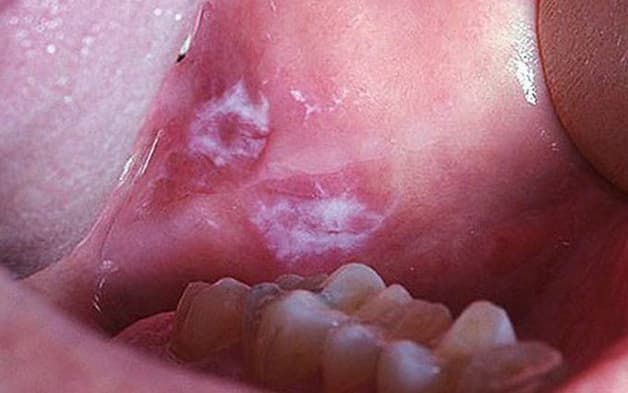

Lichen phẳng ở miệng còn được gọi với tên phát ban vùng miệng. Đây là một dạng của bệnh khi xuất hiện ở khoang miệng. Bản chất, đó là một loại bệnh da liễu. Chúng gây tác động tới màng nhầy trong niêm mạc miệng.

Có 3 dạng Lichen phẳng ở miệng: Lichen dạng lưới và Lichen dạng chợt. Trong đó:

– Lichen phẳng dạng lưới ở dưới mặt lưỡi, má và nướu răng có những nốt trắng sần sùi.

– Lichen phẳng dạng chợt là tình trạng xuất hiện các vết loét. Những vết loét này thường xuất hiện trên lưỡi, má, niêm mạc miệng hoặc nướu răng.

– Lichen phẳng dạng bóng nước là dạng hiếm gặp nhất. Khi mắc bệnh, ở khoang miệng sẽ xuất hiện những cục giống như mụn nước nổi lên. Tình trạng này xảy ra do biểu mô bị bong tróc.